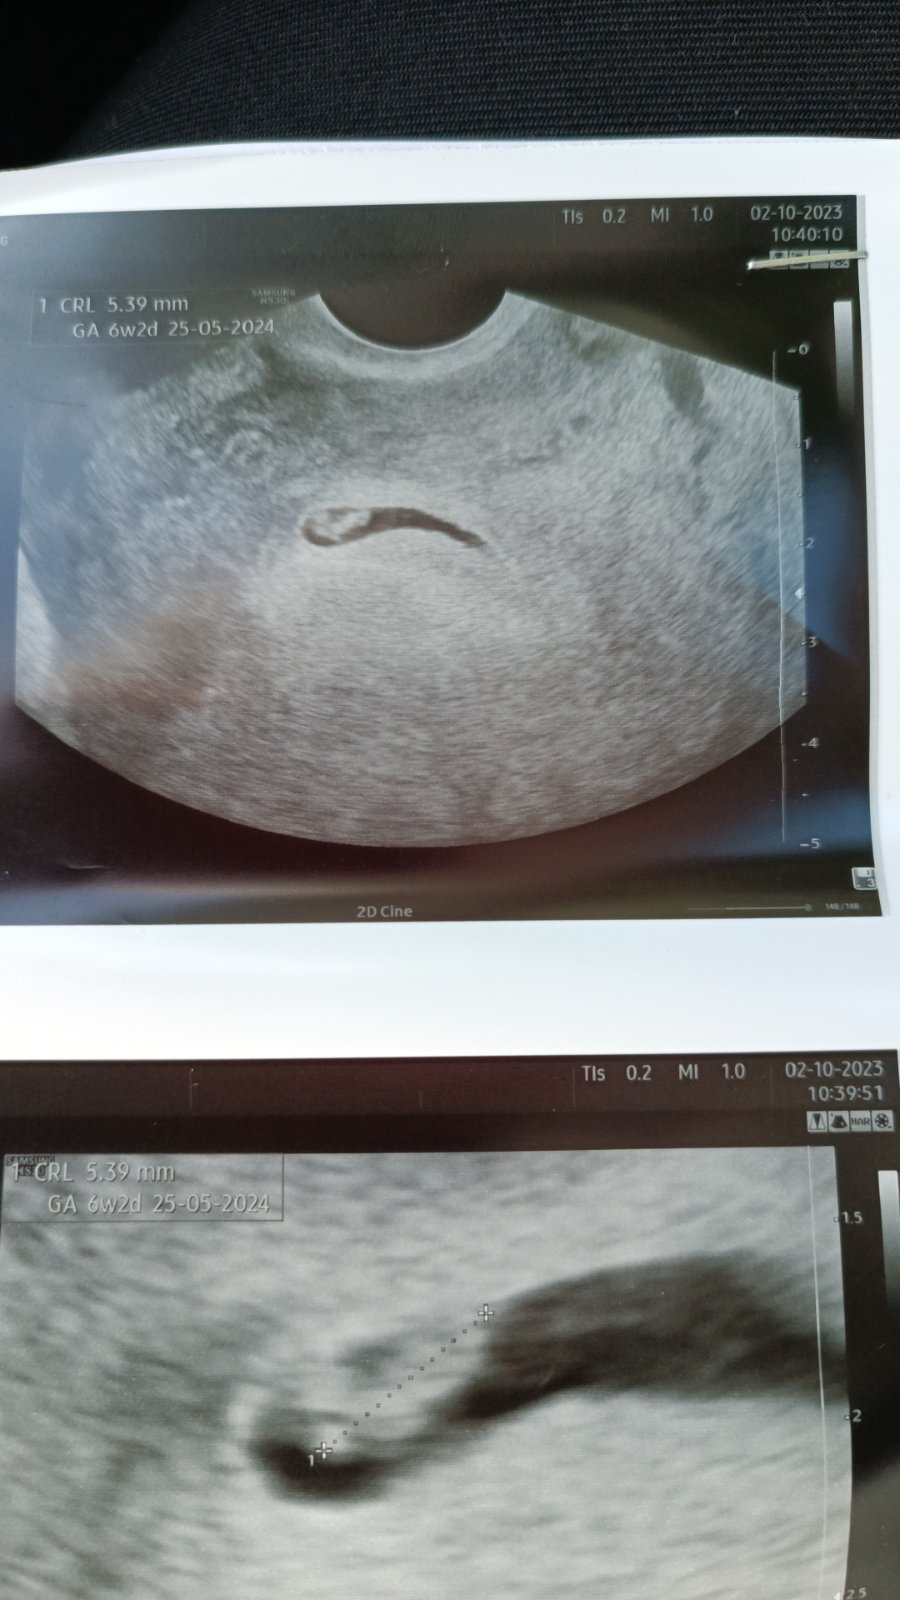

@lenie82 tak nám krásně tluče srdíčko ♥️♥️🙂 za 14 dní na další ultrazvuk . Je nám 6+2 🙏♥️